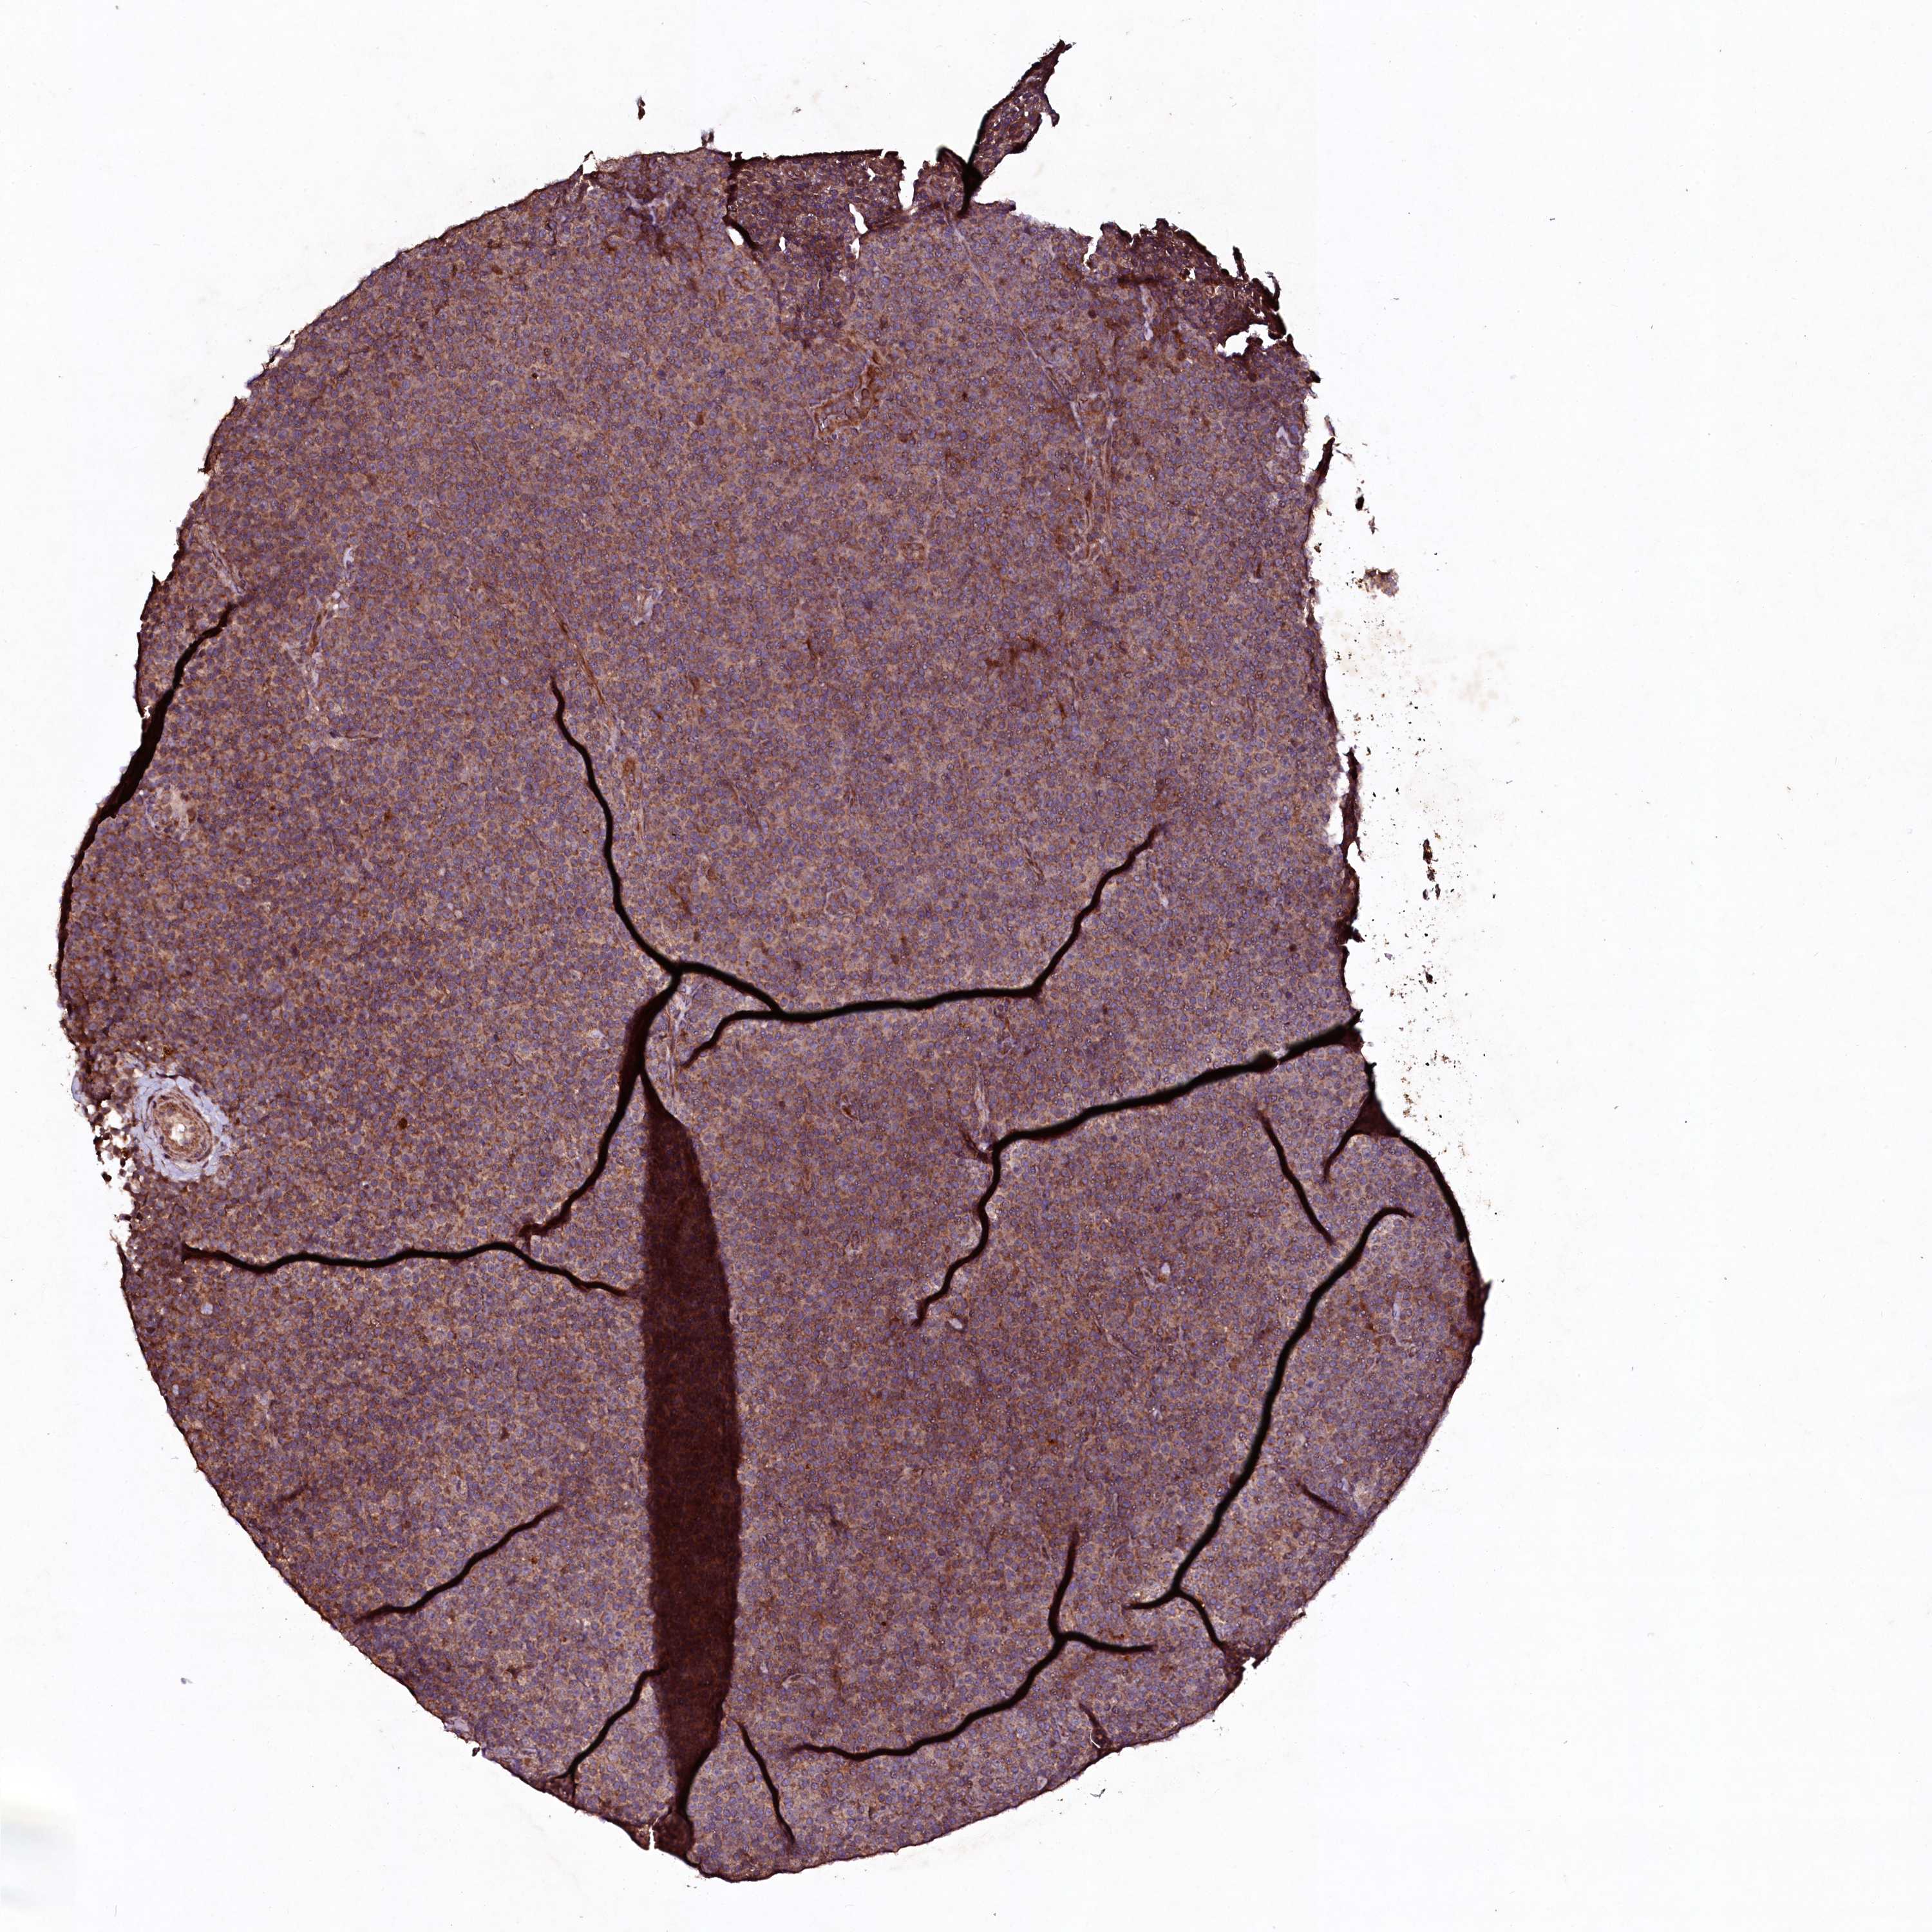

CANCER LYMPHOMA Show tissue menu

LYMPHOMA - Protein expressioni

A mouse-over function shows sample information and annotation data. Click on an image to view it in a full screen mode. Samples can be filtered based on level of antibody staining by selecting one or several of the following categories: high, medium, low and not detected. The assay and annotation is described here.

Each image is clickable and will lead to virtual microscopy that enables deeper exploration of all samples and also displays staining intensity scores, fraction scores and subcellular localization as well as patient and tissue information for each sample.

Antibody HPA040196

Hodgkin's disease, NOS

Malignant lymphoma, non-Hodgkin's type, High grade

Malignant lymphoma, non-Hodgkin's type, Low grade